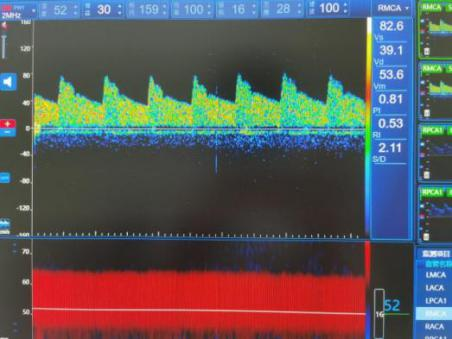

利用超声多普勒效应,以颅骨较薄部位和自然骨孔(如颞骨、枕骨大孔、眼眶等)作为检测声窗,对颅内动脉血流动力学进行评估的一项无创性检查方法,被称为脑部听诊器。

由于该检查无痛苦、无辐射、操作方便、可重复检查等优点,可以提供CT、MRI等影像技术所测不到的重要血流动力学数据,因此,它在评价脑血管疾病以及鉴别诊断方面有着重要的意义。